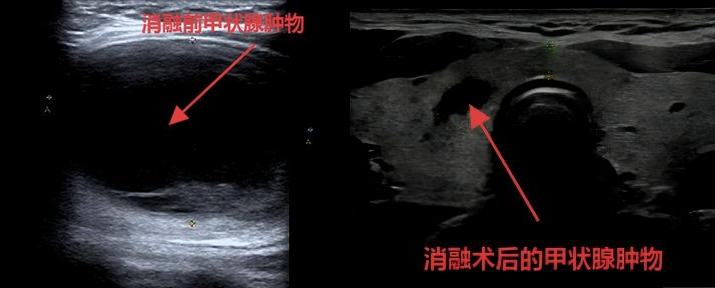

近期,甲状腺射频消融术后半年的王女士,高兴的来到甲状腺外科门诊,表示颈部鸡蛋大小的甲状腺肿物神奇的消失了,甲状腺外科安兆峰主任为王女士进行颈部查体,颈部的甲状腺肿物确实已经无法触及了,并且颈部完全没有疤痕。安主任对比了王女士半年前及现在的甲状腺彩超,半年前5cm大小的甲状腺肿物已经缩小为不到1cm的肿物。

消融治疗使得病灶的血供完全消失,结节内的细胞发生热变性、凝固性坏死。治疗后的结节已不再是病灶,而是被凝固的、坏死的消融区。消融区凝固坏死组织不断被吞噬清除、缓慢缩小。

这个过程存在一定的个体差异,受原病灶大小及患者免疫功能状态的影响,吸收时间快慢不一。相关研究报道显示,大部分甲状腺结节消融6-12个月后随访可出现明显体积缩小,少部分甚至可出现“完全消失”。